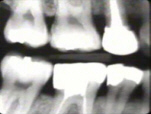

La Radiografía del lado

derecho muestra pérdida moderada del hueso periodontal con una tendencia

de bolsas infraóseas en los primeros premolares superiores.

|

La radiografía del

lado izquierdo revela pérdida moderada de hueso periodontal.